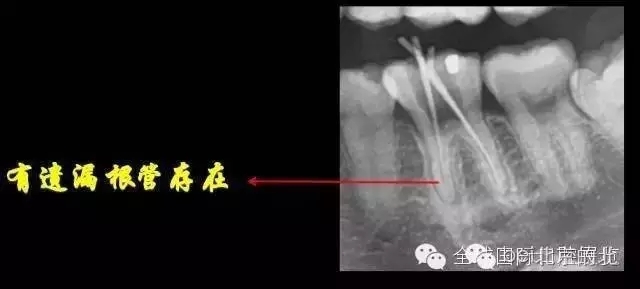

X-RAY示:近遠(yuǎn)中牙根都有陰影存在,牙周膜都有些許增寬,近中頸部位置牙體有低密度減低影,就是楔狀缺損的位置。

DB,DL.根管充填完成,樹脂封閉根管口,繼續(xù)探索未知的近中隱藏根管,所以決定拍1/4 CBCT確認(rèn)MB存在,

證實(shí)確實(shí)是遺漏了MB,